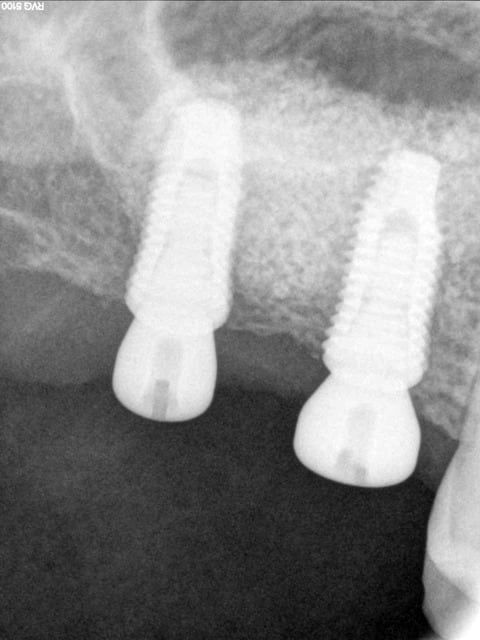

> je voulais partager avec vous ce cas de soulevé sinusien par voie latérale avec

> implantation immédiate qui est possible malgré la faible quantité osseuse

> résiduelle comme on peut s'en rendre compte sur la 3D grâce aux caractéristiques

> de l'implant.

> on peut noter sur la dernière pano qui est réalisée à 2 mois post op la

> densification du matériau qui peut s'expliquer de différentes manières:

> - la petite fenêtre réalisée (technique DASK)

> - le matériau OSTEON qui est un biphasé dont chaque particule d'HA est enrobée

> de béta TCP ce qui rend son intégration plus rapide

> voici la radio de controle ( rétro) des piliers de cicat

Normalement j'attends 9 mois quand comme dans ce cas je fais sinus et implant mais pour ce cas la patiente était un peu raide au niveau finance c'est pourquoi elle a attendu un peu plus quasi 1 an